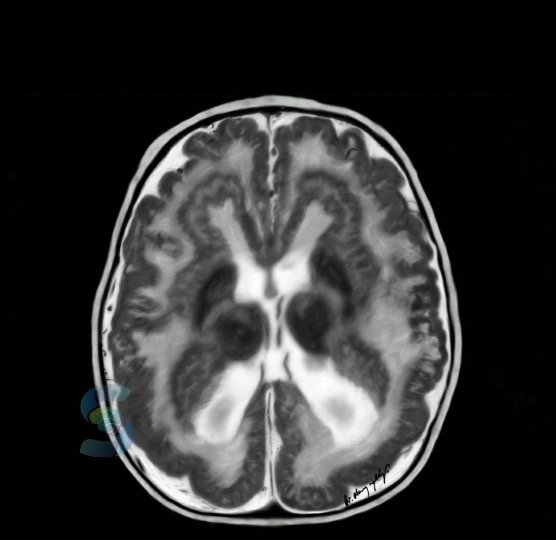

• Cortical malformations refer to structural abnormalities of the brain's cortex, which is the outermost layer of the brain responsible for various cognitive functions. These malformations arise from abnormal brain development during fetal growth and can cause a wide range of neurological symptoms, including seizures, intellectual disability, developmental delays, and motor impairments. Some of the most common types of cortical malformations include neuronal migration disorders, such as lissencephaly and heterotopia, as well as abnormal cortical organization, such as polymicrogyria and focal cortical dysplasia.